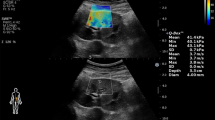

MRE detected increased stiffness in the STK medulla (15.3 ± 2.1 vs. 10.1 ± 0.8 kPa, p < 0.05) that moderately correlated with severity of fibrosis (R2 = 0.501, p < 0.01), but did not identify mild STK cortical or contralateral kidney fibrosis. Trichrome staining showed that medullary fibrosis was increased in ARAS and alleviated by SW (10.4 ± 1.8% vs. 2.9 ± 0.2%, p < 0.01). SW slightly decreased blood pressure and normalized STK RBF and GFR in ARAS. In the contralateral kidney, SW reversed the increase in RBF and GFR.

Top: Representative images and quantification of trichrome staining from contralateral medulla. SW ameliorated the increased medullary fibrosis in ARAS CLK. Bottom: Representative MRE images (yellow/red color indicates greater stiffness) from contralateral cortex and medulla (TIFF 2309 kb)